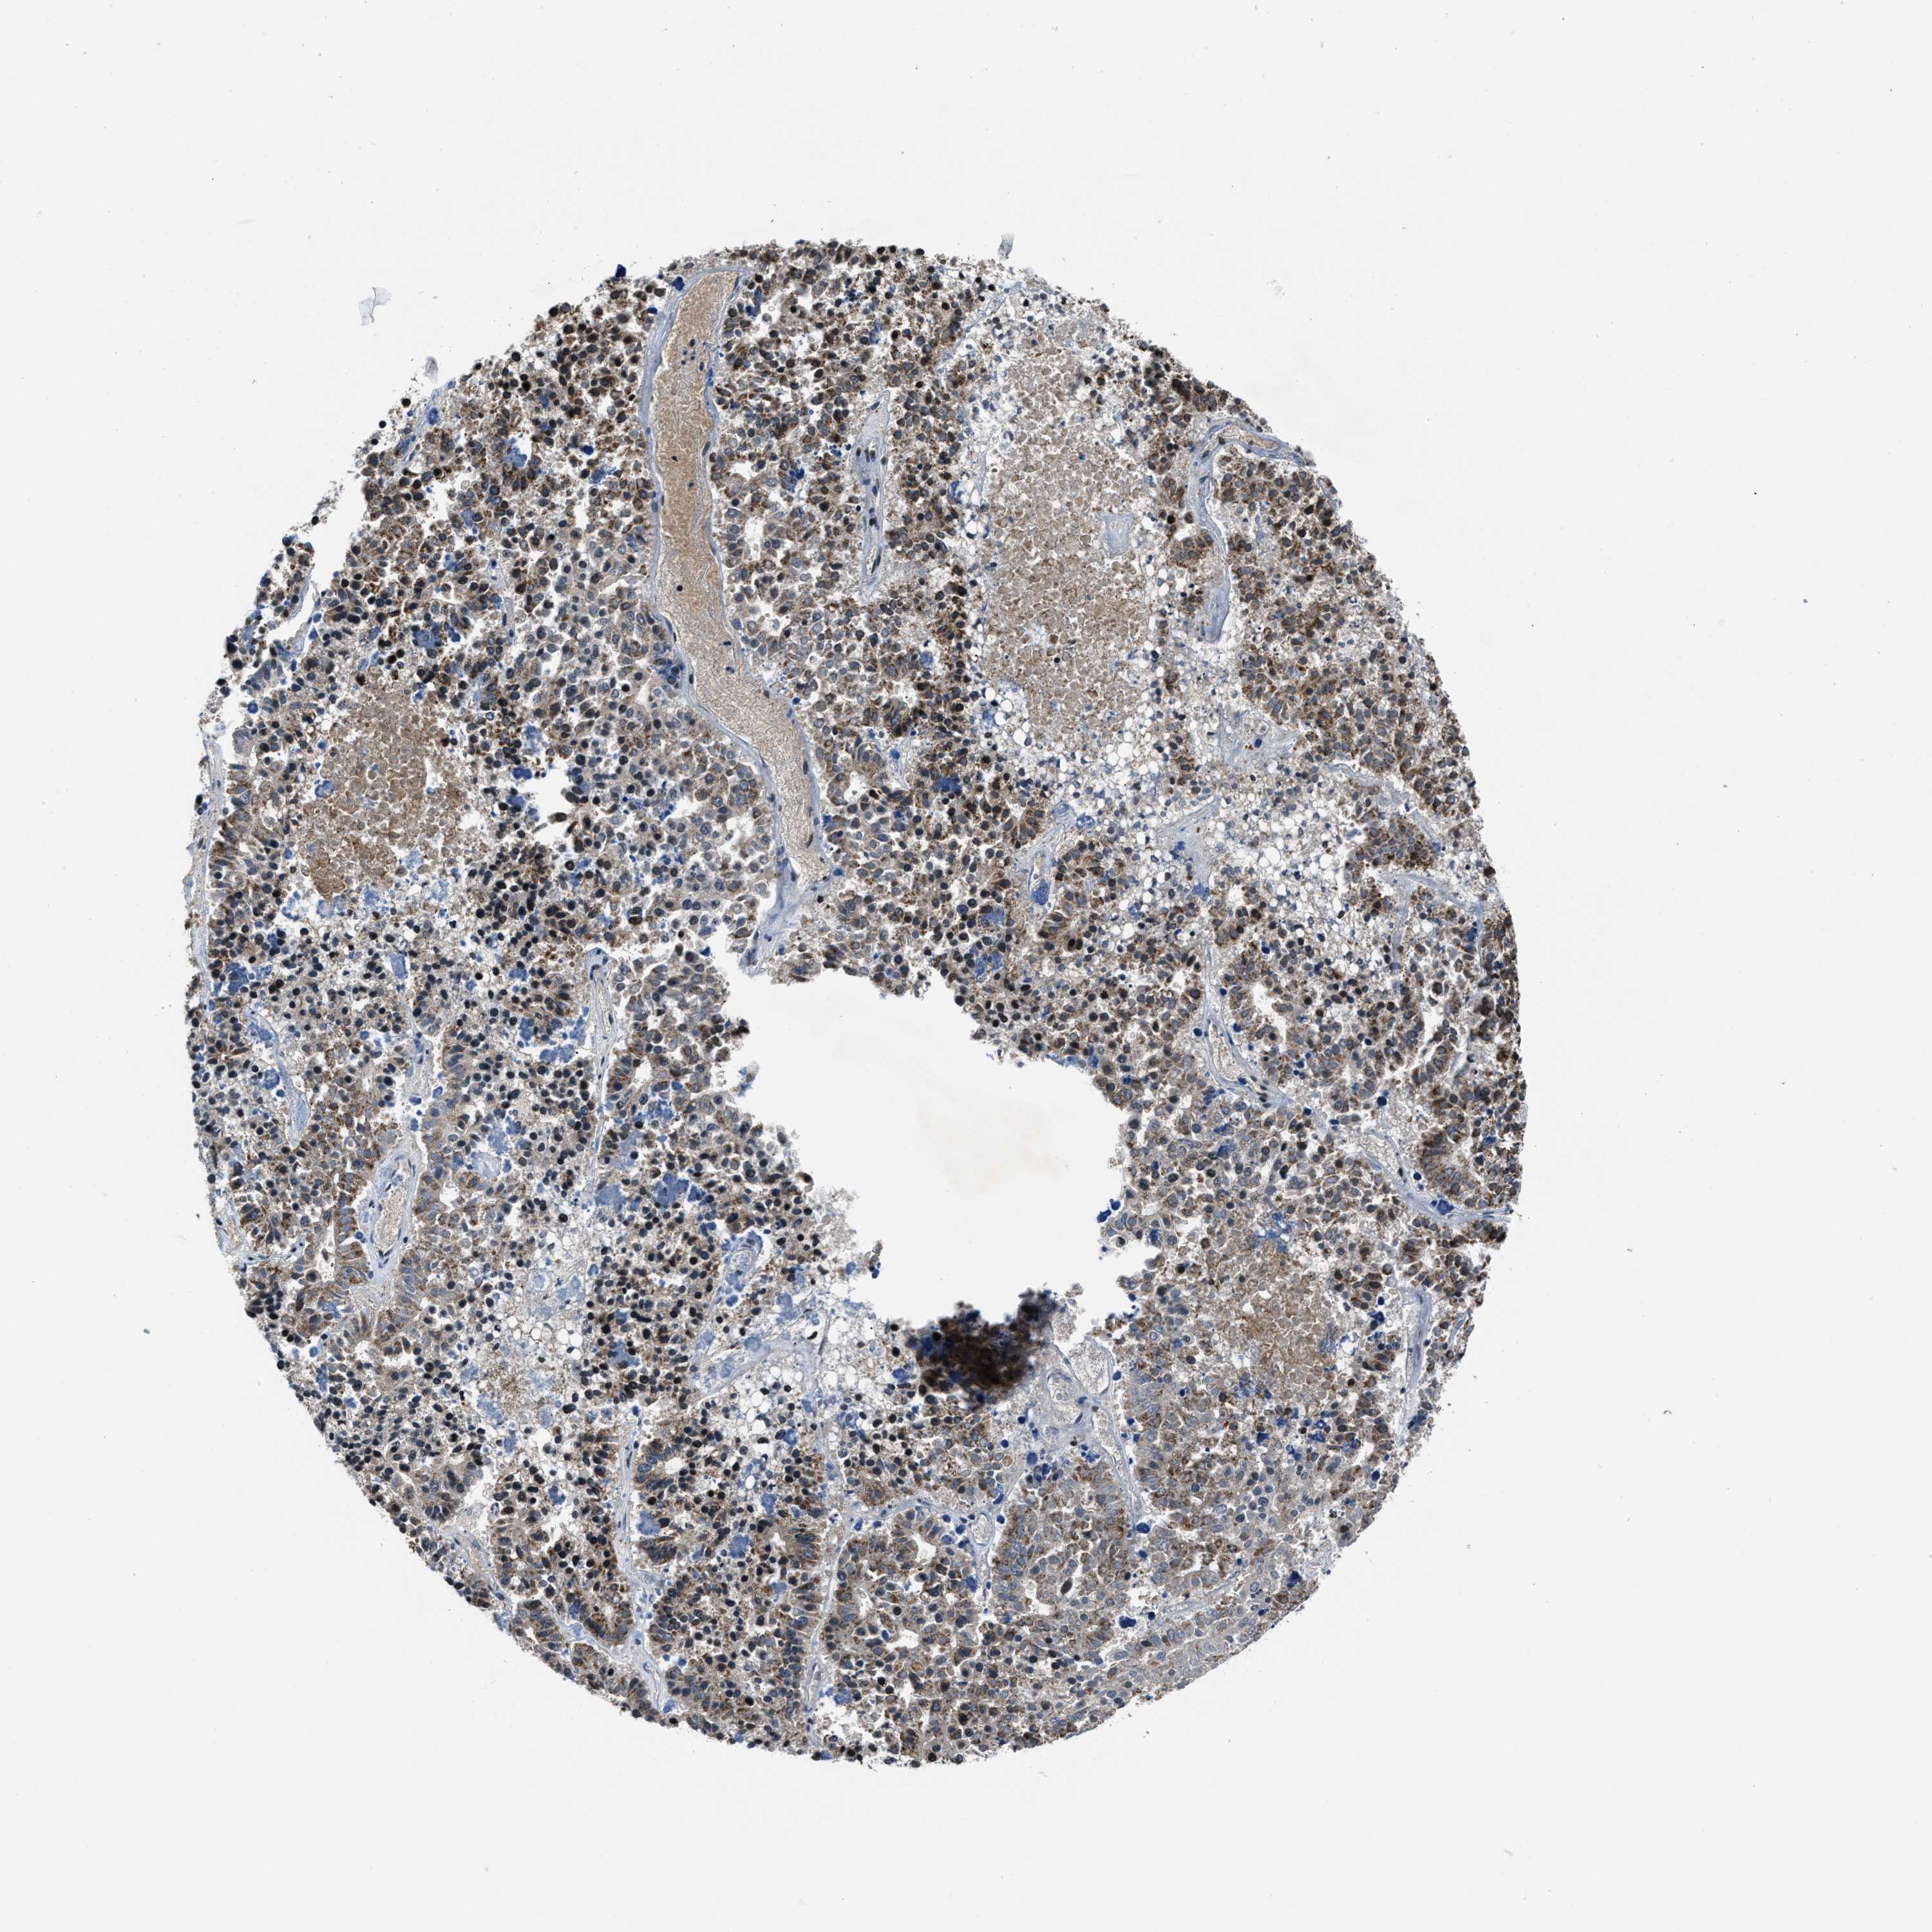

PANCREATIC CANCER - Protein expressioni

A mouse-over function shows sample information and annotation data. Click on an image to view it in a full screen mode. Samples can be filtered based on level of antibody staining by selecting one or several of the following categories: high, medium, low and not detected. The assay and annotation is described here.

Note that samples used for immunohistochemistry by the Human Protein Atlas do not correspond to samples in the TCGA dataset.

Antibody stainingi

Antibody staining in the annotated cell types in the current human tissue is reported as not detected, low, medium, or high, based on conventional immunohistochemistry profiling in selected tissues. This score is based on the combination of the staining intensity and fraction of stained cells.

Each image is clickable and will lead to virtual microscopy that enables deeper exploration of all samples and also displays staining intensity scores, fraction scores and subcellular localization as well as patient and tissue information for each sample.

Antibody HPA016450

Antibody HPA021079

Staining

High

Medium

Low

Not detected

Intensity

Strong

Moderate

Weak

Negative

Quantity

>75%

75%-25%

<25%

None

Location

Nuclear

Cytoplasmic/membranous

Cytoplasmic/membranous,nuclear

Adenocarcinoma, NOS